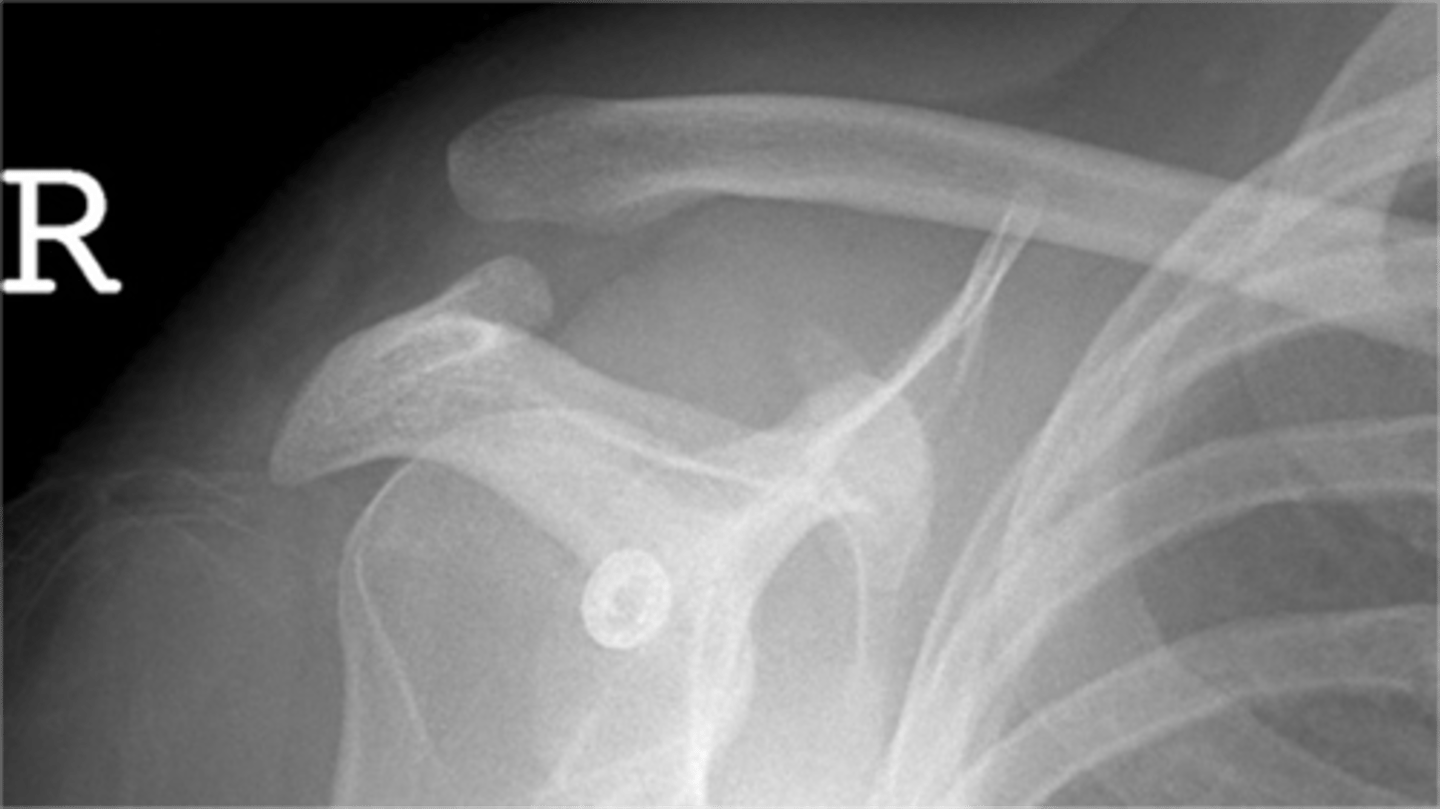

Condition: anterior GHJ dislocation

REALLY important to know BEFORE you relocate the humerus into the GHJ to know where the fracture(s) is and the integrity of the neurovascular structures

What is this image depicting? In an ideal scenario, determining this diagnosis is important before what? Why?

Condition: anterior GHJ dislocation via a Y-view -- makes dislocations MUCH more obvious

What is this image depicting? What view is it?